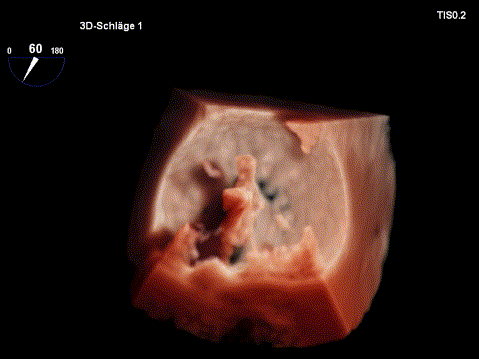

影像,火眼“晶”睛

飞利浦国产EPIQ 7C带来业内首创的TrueVue技术:TrueVue Light光源心腔镜,光影变化,可透过表面看本质,真实还原心脏立体结构,协助准确诊疗;TrueVue Color彩色心腔镜,血流溯源,更直观、准确的显示心脏血流动力学形态,带来全方位的极致体验。

图片

TrueVue Color彩色心腔镜